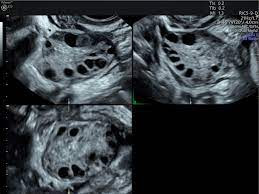

blood tests to measure hormone levels to determine ovulation. An imaging test (Ultrasound

Pelvis) to look for uterine or fallopian tube diseases and ovarian reserve testing

to determine the quality and quantity of eggs available for ovulation. Hysterosalpingography